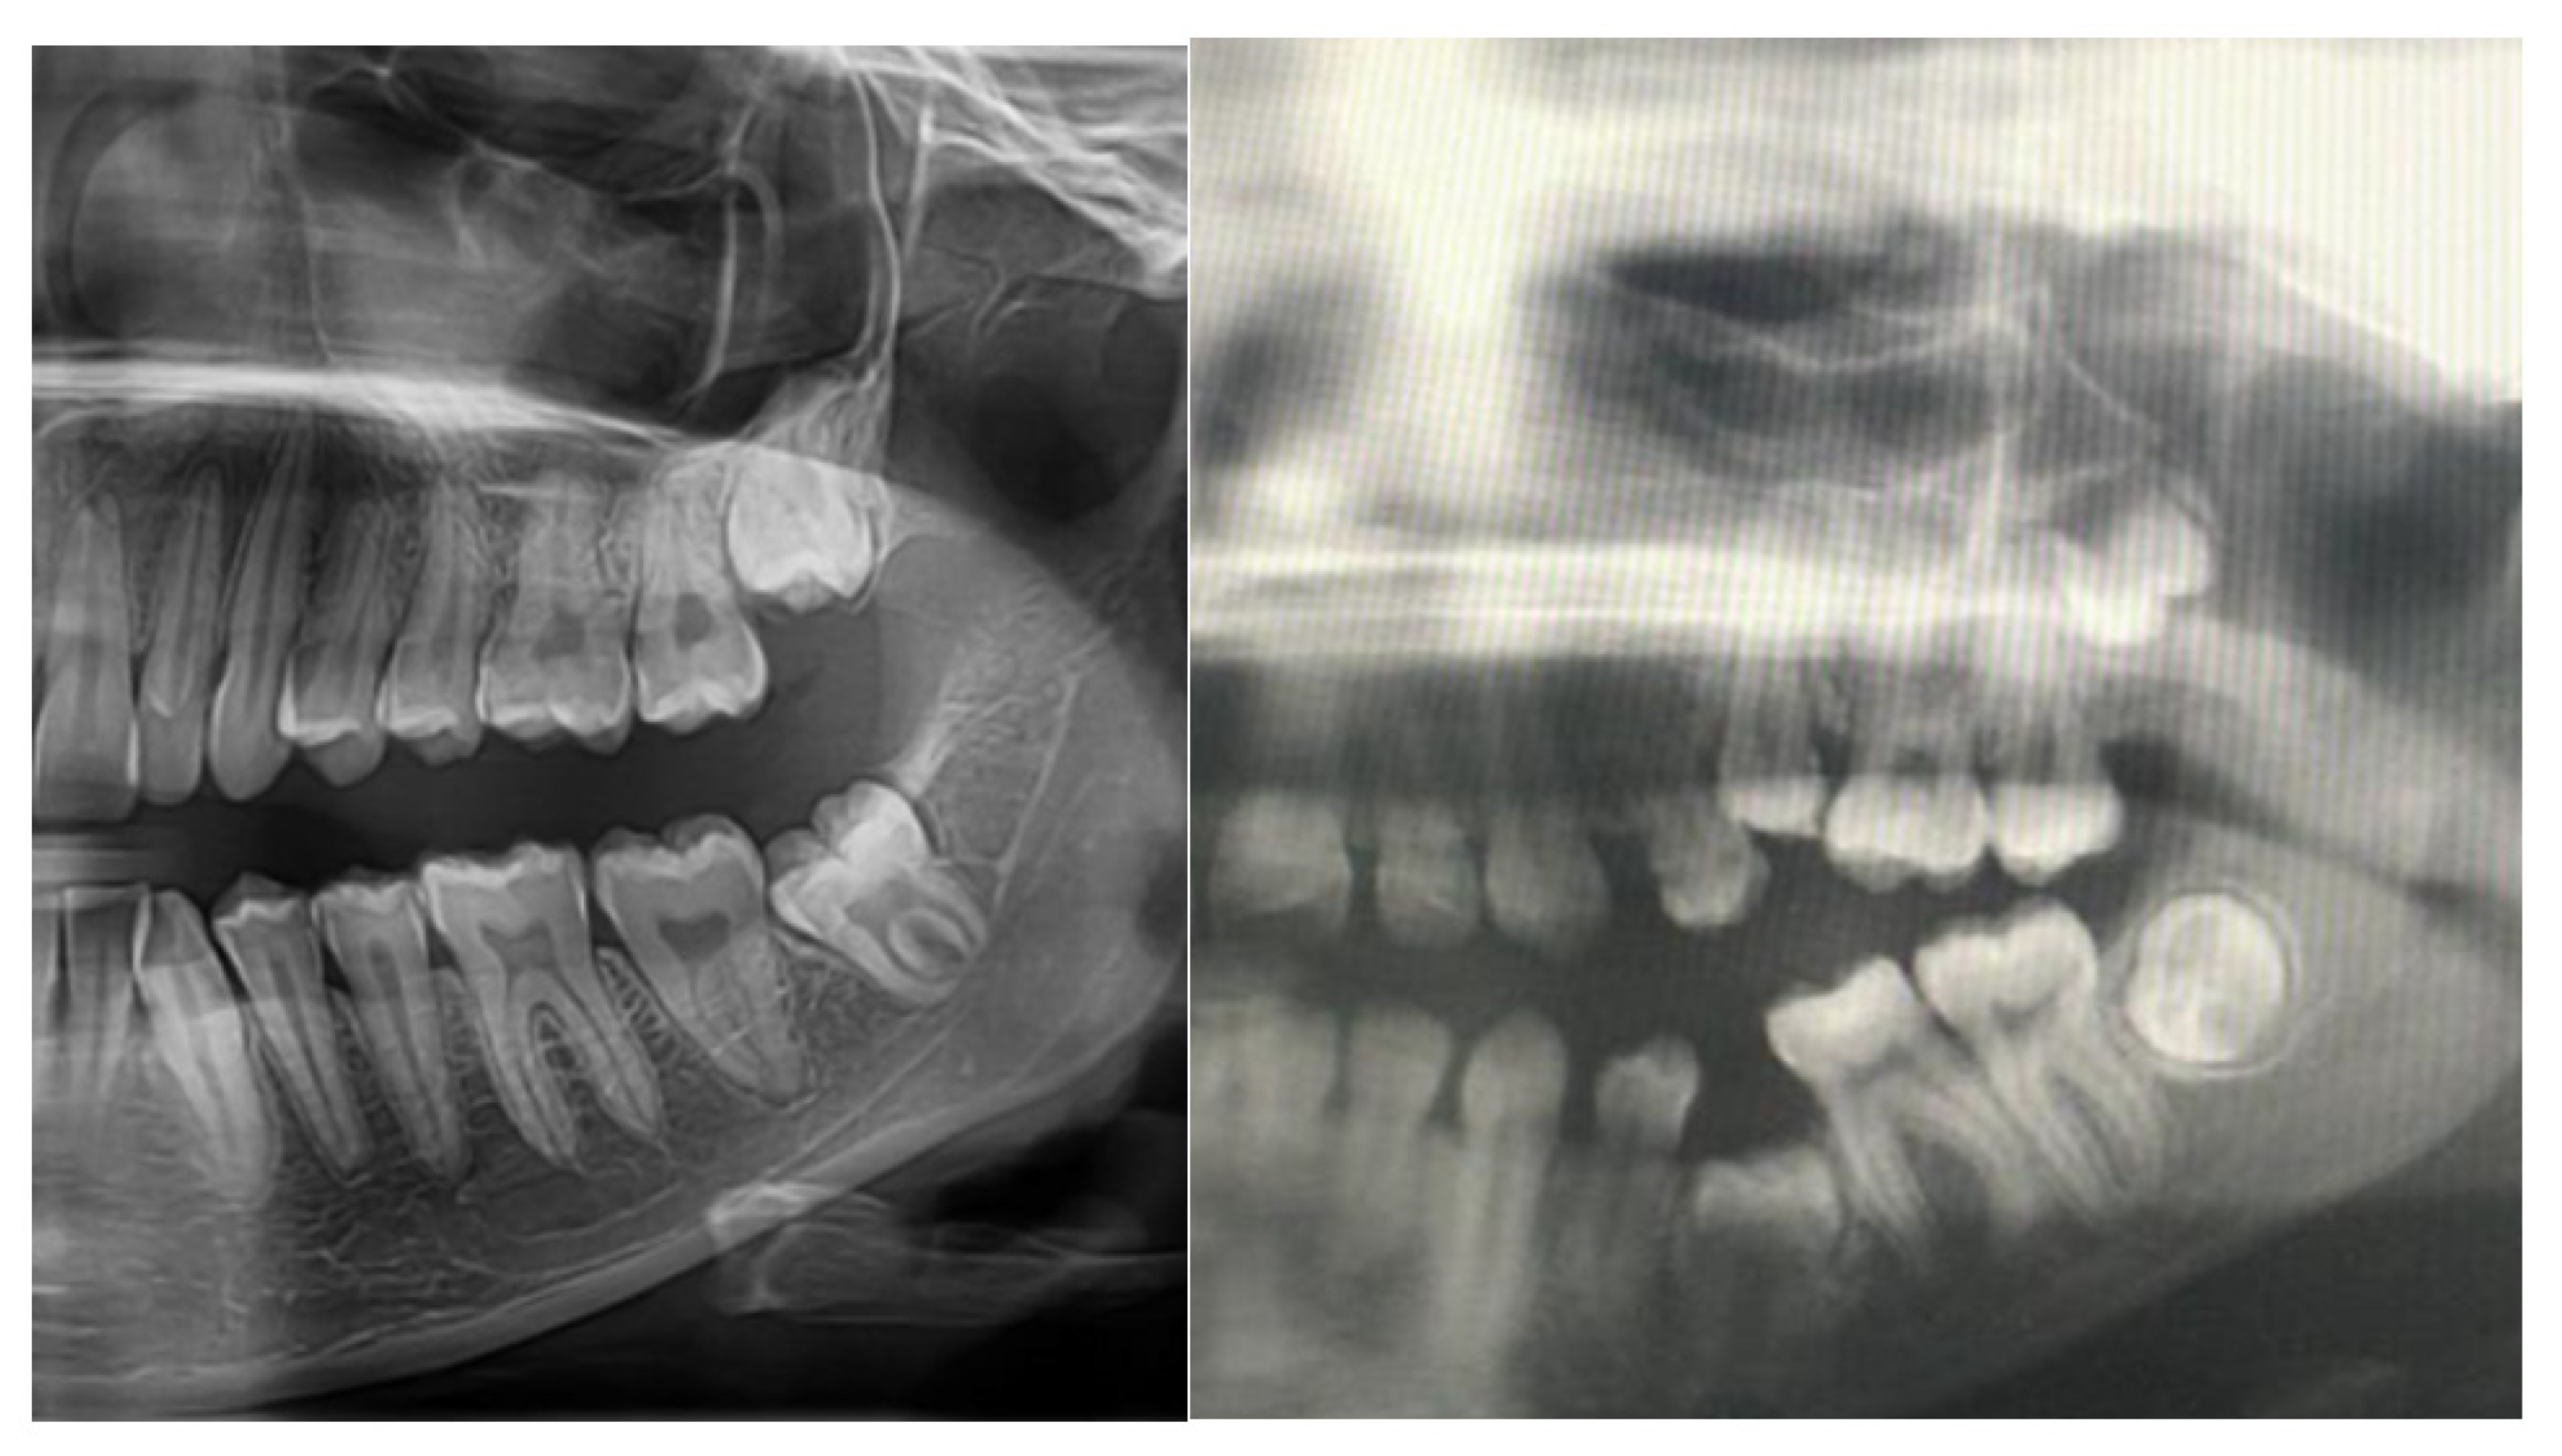

2.3. Pathogenesis of Dental Abnormalities

- Akleyin, E.; Polat, Y.; Yavuz, Y. Three-Year Dentition Follow-up of a Paediatric Case with Malignant Infantile Osteopetrosis: A Review of the Literature. J. Clin. Trials Exp. Investig. 2022, 1, 41–48. [Google Scholar]